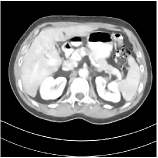

We have conducted experiments on 20 test slices (slice 20, slice 50, slice 100, slice 150 and slice 200 of patient L067, L143, L192, L310) of the Mayo Clinic data. Table I shows the averaged image quality of 20 test images with different methods. From Table I, we observe that Parallel SUPER significantly improves the image quality compared with the standalone methods. It also achieves 1.8 HU better average RMSE compared with Serial SUPER while its SSIM is comparable with Serial SUPER. Fig. 3 shows the reconstructions of L067 (slice 50) and L310 (slice 150) using PWLS-ULTRA, FBPConvNet, serial SUPER (FBPConvNet + PWLS-ULTRA), and parallel SUPER (FBPConvNet + PWLS-ULTRA), along with the references (ground truth). The Parallel SUPER scheme achieved the lowest RMSE and the zoom-in areas show that Parallel SUPER can reconstruct image details better.